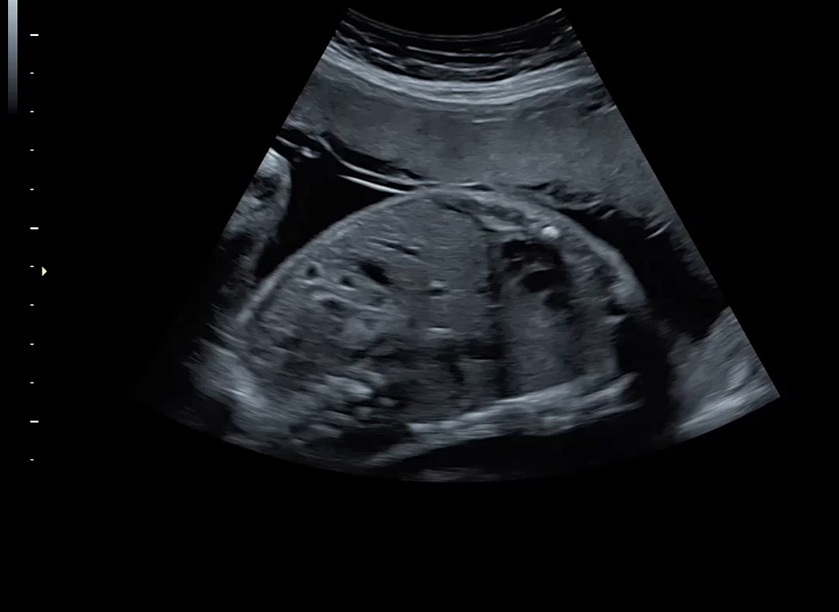

Ультразвуковая платформа Voluson S8 представляет собой оборудование экспертного класса с передовыми возможностями и высоким уровнем автоматизации процессов. Она позволяет проводить сканирование в режимах 2D, 3D и 4D с высоким качеством изображений.

• Высокое качество изображений: Voluson S8 обеспечивает высококачественные изображения, позволяющие детально оценить состояние плода и обнаружить возможные патологии.

• Высокочувствительные датчики: Ультразвуковой сканер Voluson S8 оснащен высокочувствительными датчиками, что позволяет проводить полноценное обследование даже у пациентов с сложными анатомическими особенностями.

• Технология SonoRenderlive: Эта технология облегчает получение 3D/4D изображений путем автоматического изменения положения плоскости визуализации в зависимости от движений плода. Она позволяет получить реалистичные и объемные изображения, что полезно для демонстрации плода будущим родителям и для дополнительного анализа.